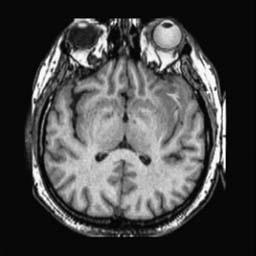

To demonstrate the effectiveness and efficiency of the proposed image fusion method , we conduct a set of comparative experiments on three image datasets. The first is composed by 8 pairs of multi-modal medical images and the second one contains 15 pairs of multi-focus gray or color natural images. These two datasets are often used in many related papers and some examples are shown in Figure 3(a) and Figure 3(b). The third one is a new multi-focus cervical cell image dataset collected by ourselves, which consists of 15 groups of color images and each group contains a series of multi-focus cervix cell images with size of or , etc. Some source examples are shown in Figure 3(c). Our source code implemented in C++ along with the new multi-focus cervical cell image dataset is available online.

We first evaluate the performance of the proposed method under varying total number of octaves and number of layers sampled per octave. The fused images of a pair of multi-modal medical images with different and are shown in Figure 4. In this example, on the one hand, when only 1 or 2 octaves are involved in constructing the DoG pyramid, the fused images fail to keep the integrity information of large size objects (e.g. eyeballs), while by increasing the value of , the integrity information of eyeballs is preserved. On the other hand, although not as significant as the increase of octave numbers , the fused image can contain more details by the increase of layer numbers . The corresponding objective quality metrics are shown in Figure 5. As shown in Figure 5(a), most of the metric values are improved as the number of octaves increases with the fixed layer numbers 3 in the global tendency and each of them tends to be stable when the number of octaves is 5. To get a relatively good quality from Figure 5(b), we can notice that some of the metric values can get a good performance when the number of layers is 3, such as the MI, SSIM, QI and VIF, though there are only a little change of all the metric values by increasing the number of layers with the fixed octave numbers 5. Because it will result in more computation burden with the increase of the value and , and for different kinds of source images, there are different performance with the diverse parameter settings. To get a trade-off between them in our experiments, we set for the multi-modal dataset, for the natural datasets and for the multi-focus cell dataset, respectively.

Figure 6 shows the fused images obtained by different methods with the multi-modal source images shown in Figure 3(a). As shown in these figures, the proposed method can produce images which preserve the complementary information of different source images well. Moreover, due to the scale-invariant structure saliency selection, our method can keep the integrity information of large size objects and the visual details simultaneously. Although the fused image generated by other methods can also capture the details to some extent, all of them fail to keep the integrity information of large size objects such as the eyeballs. Furthermore, from Figure 6(k)-6(t), the DTCWT, GFF, IM and NSCT methods may decrease the brightness and contrast while the proposed method can preserve these features and details without producing visible artifacts and brightness distortions.